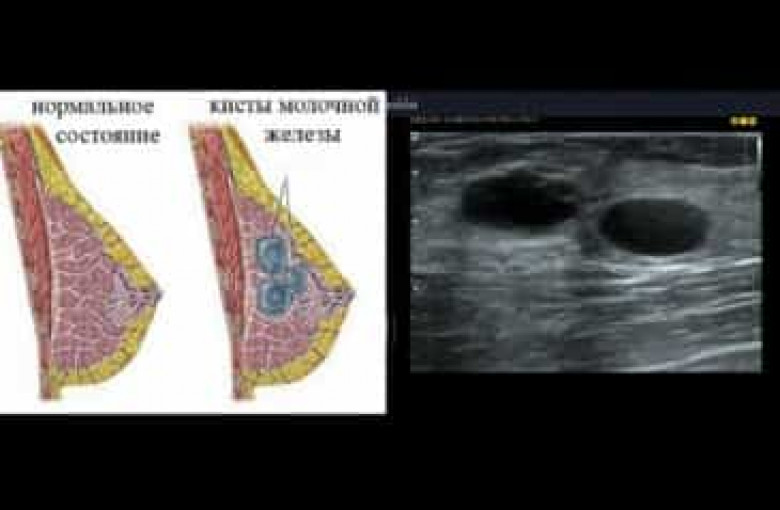

ԼԱՅՖԿրծքագեղձի կիստան վերարտադրողական տարիքում գտնվող կանանց մոտ առաջացող բարորակ գոյացություն է, որն իրենից ներկայացնում է հեղուկով լցված պարկիկ: Կիստայի չափերը կարող են տարբեր լինել՝ մեկ միլիմետրից՝ մինչև մի քանի սանտիմետր: